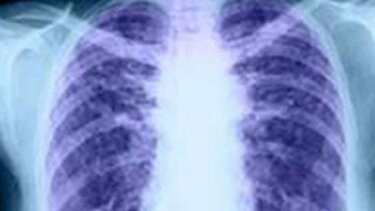

Εκστρατεία ενημέρωσης για την Ιδιοπαθή Πνευμονική Ίνωση υλοποιεί για μία ακόμη χρονιά, τέταρτη στη σειρά, η Ελληνική Πνευμονολογική Εταιρεία.

Με κεντρικό μήνυμα «ΖΩντας με μία χρόνια νόσο – Κάθε ανάσα, μια ιστορία», η εκστρατεία της ΕΠΕ δεν εστιάζει απλώς στα επιστημονικά δεδομένα, αλλά επίσης αναδεικνύει τον ανθρώπινο παράγοντα πίσω από τη νόσο.